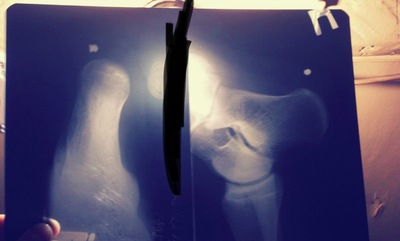

Рентген пятки полезная вещь. И еда для космонавтов нормальная по вкусу. Не такая чтоб каждый день есть, но вполне себе можно перекусить если что.

А насчет рентгена - нельзя же часто его делать, облучение и всё такое